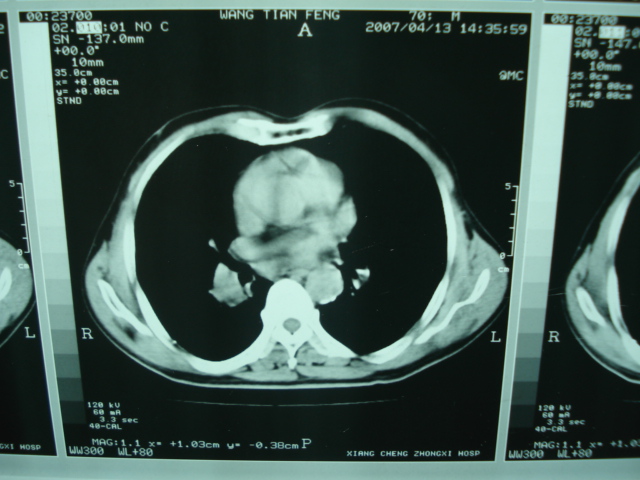

以下是引用狙击手在2007-4-18 20:17:00的发言:[br]原:2007/1/22号ct片:右肺上叶可见片状、云雾状高密度影,右肺上叶后段可见三角形高密度影,尖端指向肺门,右肺上叶后段支气管壁不规则增厚,管腔不规则增厚,纵隔未见肿大淋巴结.[br] 今ct:右肺上叶片状影增大,右肺上叶后段不张及右肺上叶后段支气管壁不规则增厚未见变化,右肺下叶背段支气管壁不规则增厚.[br] 如果考虑肺结核,但从临床证据看竟然没有一项支持肺结核,不知患者是否已经过正规抗结核治疗。没有的话,3个月了前后片看起来变化不大,似乎有不太符合肿瘤征象,不知患者是否抗炎治疗过,下叶支气管增粗还是要高度警惕,同意楼主意见,将常规病理,生化检查再做一遍。[br]

以下是引用狙击手在2007-4-18 20:17:00的发言:[br]原:2007/1/22号ct片:右肺上叶可见片状、云雾状高密度影,右肺上叶后段可见三角形高密度影,尖端指向肺门,右肺上叶后段支气管壁不规则增厚,管腔不规则增厚,纵隔未见肿大淋巴结.[br] 今ct:右肺上叶片状影增大,右肺上叶后段不张及右肺上叶后段支气管壁不规则增厚未见变化,右肺下叶背段支气管壁不规则增厚.[br] 如果考虑肺结核,但从临床证据看竟然没有一项支持肺结核,不知患者是否已经过正规抗结核治疗。没有的话,3个月了前后片看起来变化不大,似乎有不太符合肿瘤征象,不知患者是否抗炎治疗过,下叶支气管增粗还是要高度警惕,同意楼主意见,将常规病理,生化检查在做一遍。[br]